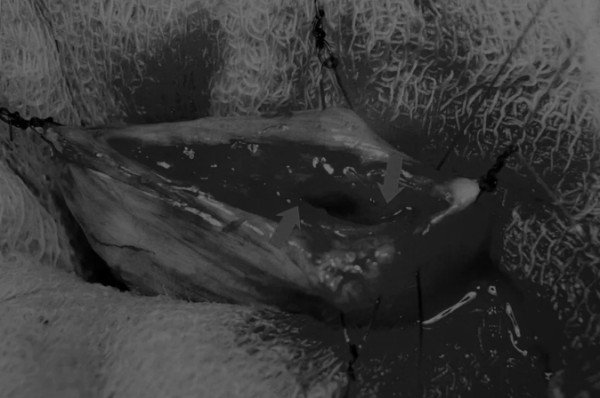

在中线开腹手术后,确定膀胱,将其取出并隔离(图1)。为了使膀胱持续暴露,可在膀胱中线两侧各放置一根固定缝线(图2)。

在牵引缝线之间选择血管扩张较差的区域用手术刀切开膀胱壁(图3)。在牵引缝合线之间用手术刀在血管不良的区域做切口。切开膀胱壁后,膀胱内的手术可按手术方案实施,例如取出结石(图4)。